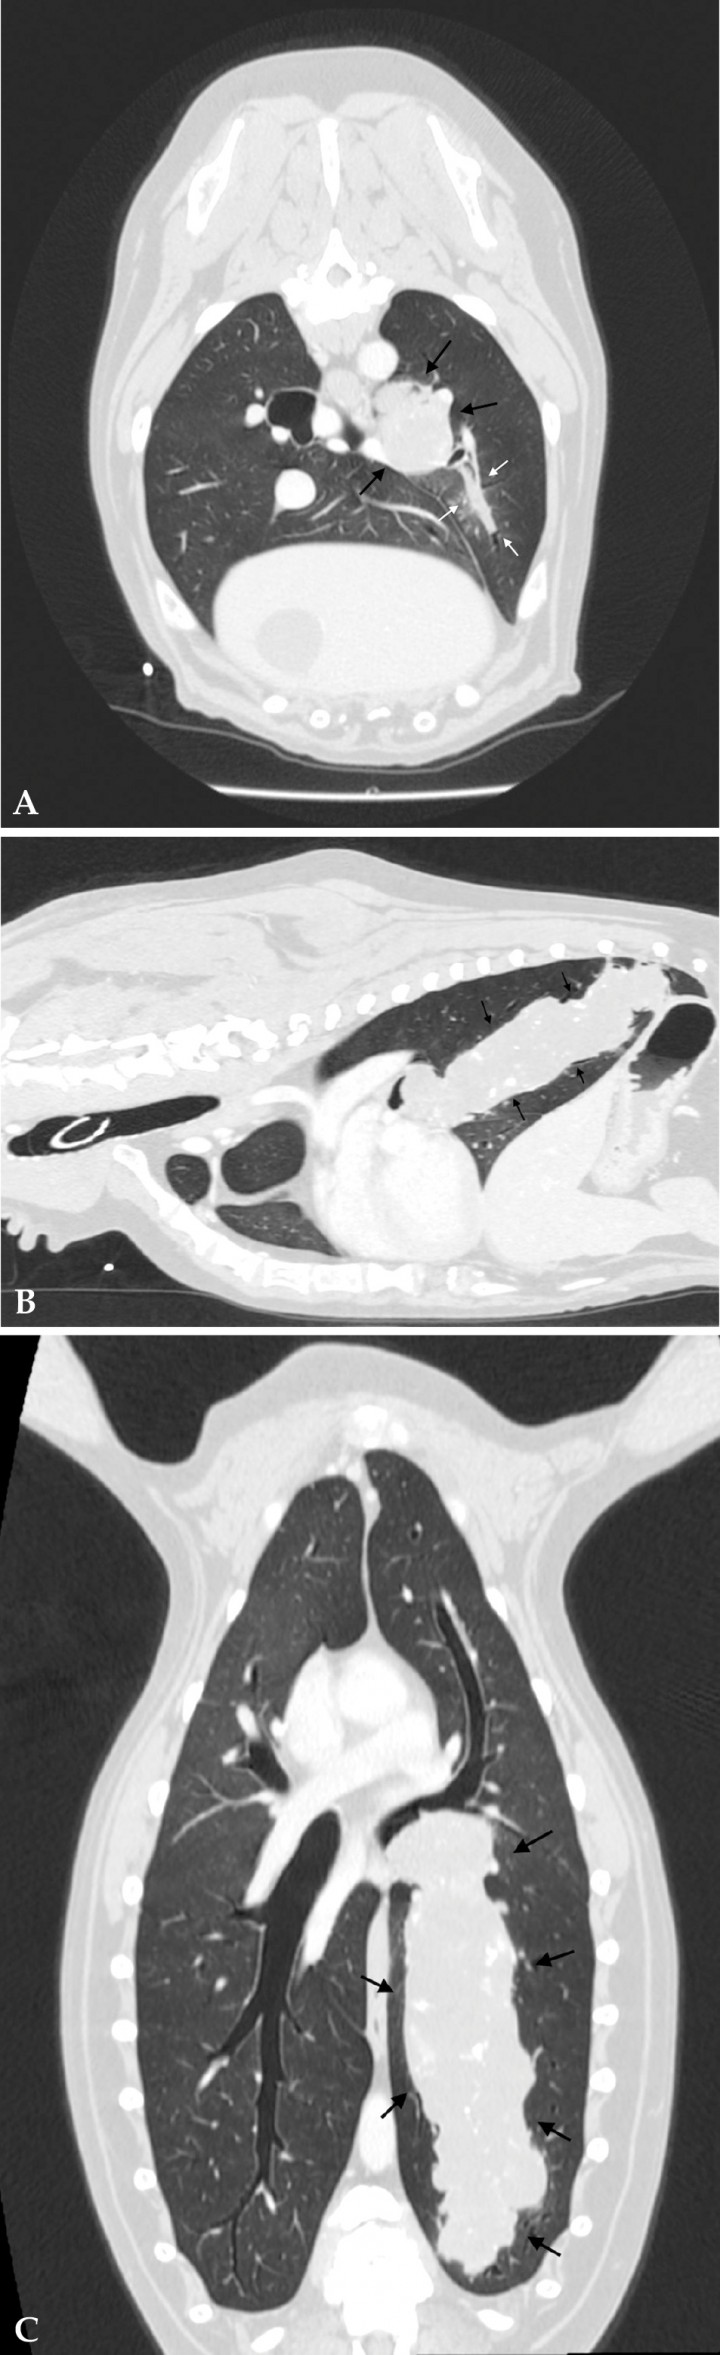

En este caso se realizó una tomografía computarizada de tórax (TC), en la que se observó una masa isoatenuante con mineralización distrófica, cilíndrica, que obstruía y expandía la práctica totalidad de la luz del bronquio caudal izquierdo (Fig. 3), extendiéndose hacia bronquiolos secundarios, con captación de contraste intravenoso pobre y heterogénea. No se observaron nódulos de metástasis en el parénquima pulmonar, linfadenopatía traqueobronquial ni efusión pleural asociadas (Fig. 4) Dada su localización en el lóbulo caudal y su distribución broncocéntrica, así como la ausencia de otras alteraciones en el parénquima pulmonar, bronquios o linfonodos, el diagnóstico diferencial que se consideró más probable fue el de una neoplasia pulmonar primaria y, concretamente, un carcinoma broncoalveolar. Se recomendó su estudio histopatológico para su caracterización definitiva.

<p>Imágenes de TC de tórax en ventana de pulmón postcontraste. (A) Plano axial. (B) Plano sagital. (C) Plano dorsal. La luz del bronquio caudal izquierdo se encuentra prácticamente obstruida por una masa isoatenuante con mineralización distrófica y cilíndrica (flechas negras) que se extiende hacia bronquiolos secundarios (flechas blancas). La captación de contraste intravenoso es pobre y heterogénea.</p>

Imágenes de TC de tórax en ventana de pulmón postcontraste. (A) Plano axial. (B) Plano sagital. (C) Plano dorsal. La luz del bronquio caudal izquierdo se encuentra prácticamente obstruida por una masa isoatenuante con mineralización distrófica y cilíndrica (flechas negras) que se extiende hacia bronquiolos secundarios (flechas blancas). La captación de contraste intravenoso es pobre y heterogénea.